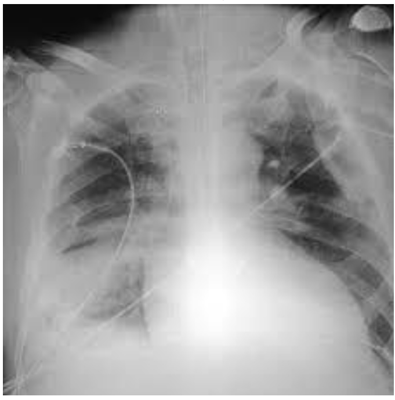

Paciente idoso, acamado, com demência de Alzheimer avançada, foi encaminhado ao pronto-socorro devido a tosse com expectoração e hipoatividade. Na chegada, apresentava sinais vitais estáveis, exceto por estertor crepitante em hemitórax direito. Foi realizado RX, com o seguinte achado. Cite a(s) medicação(ões) que deve(m) ser prescrita(s) no tratamento dessa patologia.